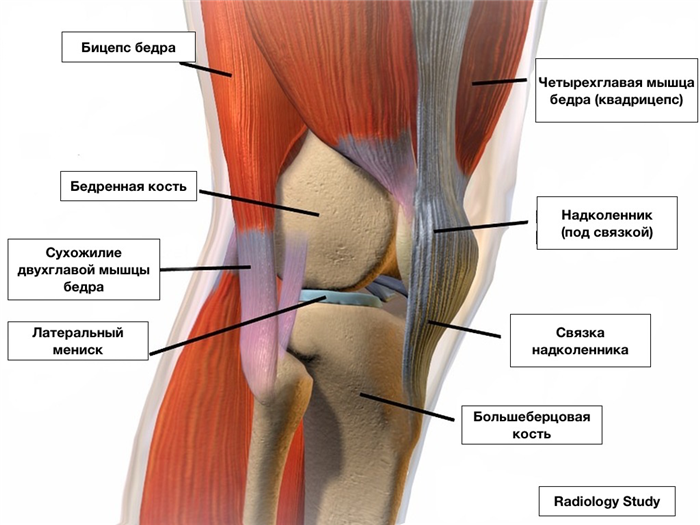

Мениски — анатомия

Артикулирующие поверхности на большеберцовой кости не соответствуют таковой на бедренной кости. Равномерному распределению давления на единицу площади в соответствующих пределах и способствуют, очевидно, такие анатомические образования, как мениски.

Мениски — две подвижные хрящевые прокладки серповидной формы, расположенные между суставными поверхностями периферических отделов бедренной и большеберцовой костей. Мениски обеспечивают конгруэнтность сочленяющихся суставных поверхностей КС, выполняют важную буферную роль, принимая на себя значительную часть нагрузки, передающейся через сустав, являются важным стабилизирующим его элементом, участвуют в обеспечении питания и смазки сустава.

Утолщенный периферический край мениска (васкуляризированная зона) крепится к суставной капсуле, которая в задних отделах образует глубокие карманы, а на уровне задненаружного угла наружного мениска прерывается входом в канал сухожилия подколенной мышцы. Тонкий свободный край мениска (аваскулярная часть) обращен в полость сустава и при дискоидном строении наружного мениска достигает межмыщелковой области. Оба мениска прочно соединены со связками в области передних и задних рогов, а внутренние — также с боковой связкой на уровне тела. Меньшая подвижность внутреннего мениска по сравнению с наружным обусловливает большую частоту его повреждения (в 8 — 9 раз).